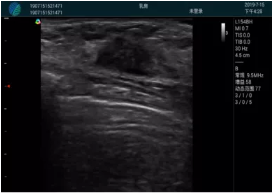

可視化甲狀腺穿刺引導(dǎo)

頸動(dòng)脈血流充盈飽滿,無外溢

肝內(nèi)血管顯示清晰,血流敏感無外溢

甲狀腺囊性結(jié)節(jié),囊壁鈣化,透聲好

甲狀腺囊性占位

2001年美國健康護(hù)理研究和質(zhì)量監(jiān)督局(AHRQ)批準(zhǔn)了一項(xiàng)關(guān)于提高患者安全性的報(bào)告,建議:在頸內(nèi)靜脈中心置管術(shù)時(shí)使用超聲引導(dǎo)。此后超聲引導(dǎo)穿刺被用于幾乎所有的急診穿刺操作,尤其是血管穿刺。